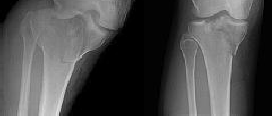

Figures 1 through 3 are the radiographs of a 25-year-old man who is brought to the emergency department after a motorcycle collision. He is complaining of isolated knee pain. Examination reveals swelling, popliteal ecchymosis, joint line pain, and limited knee joint motion. His pulses and sensation are normal.